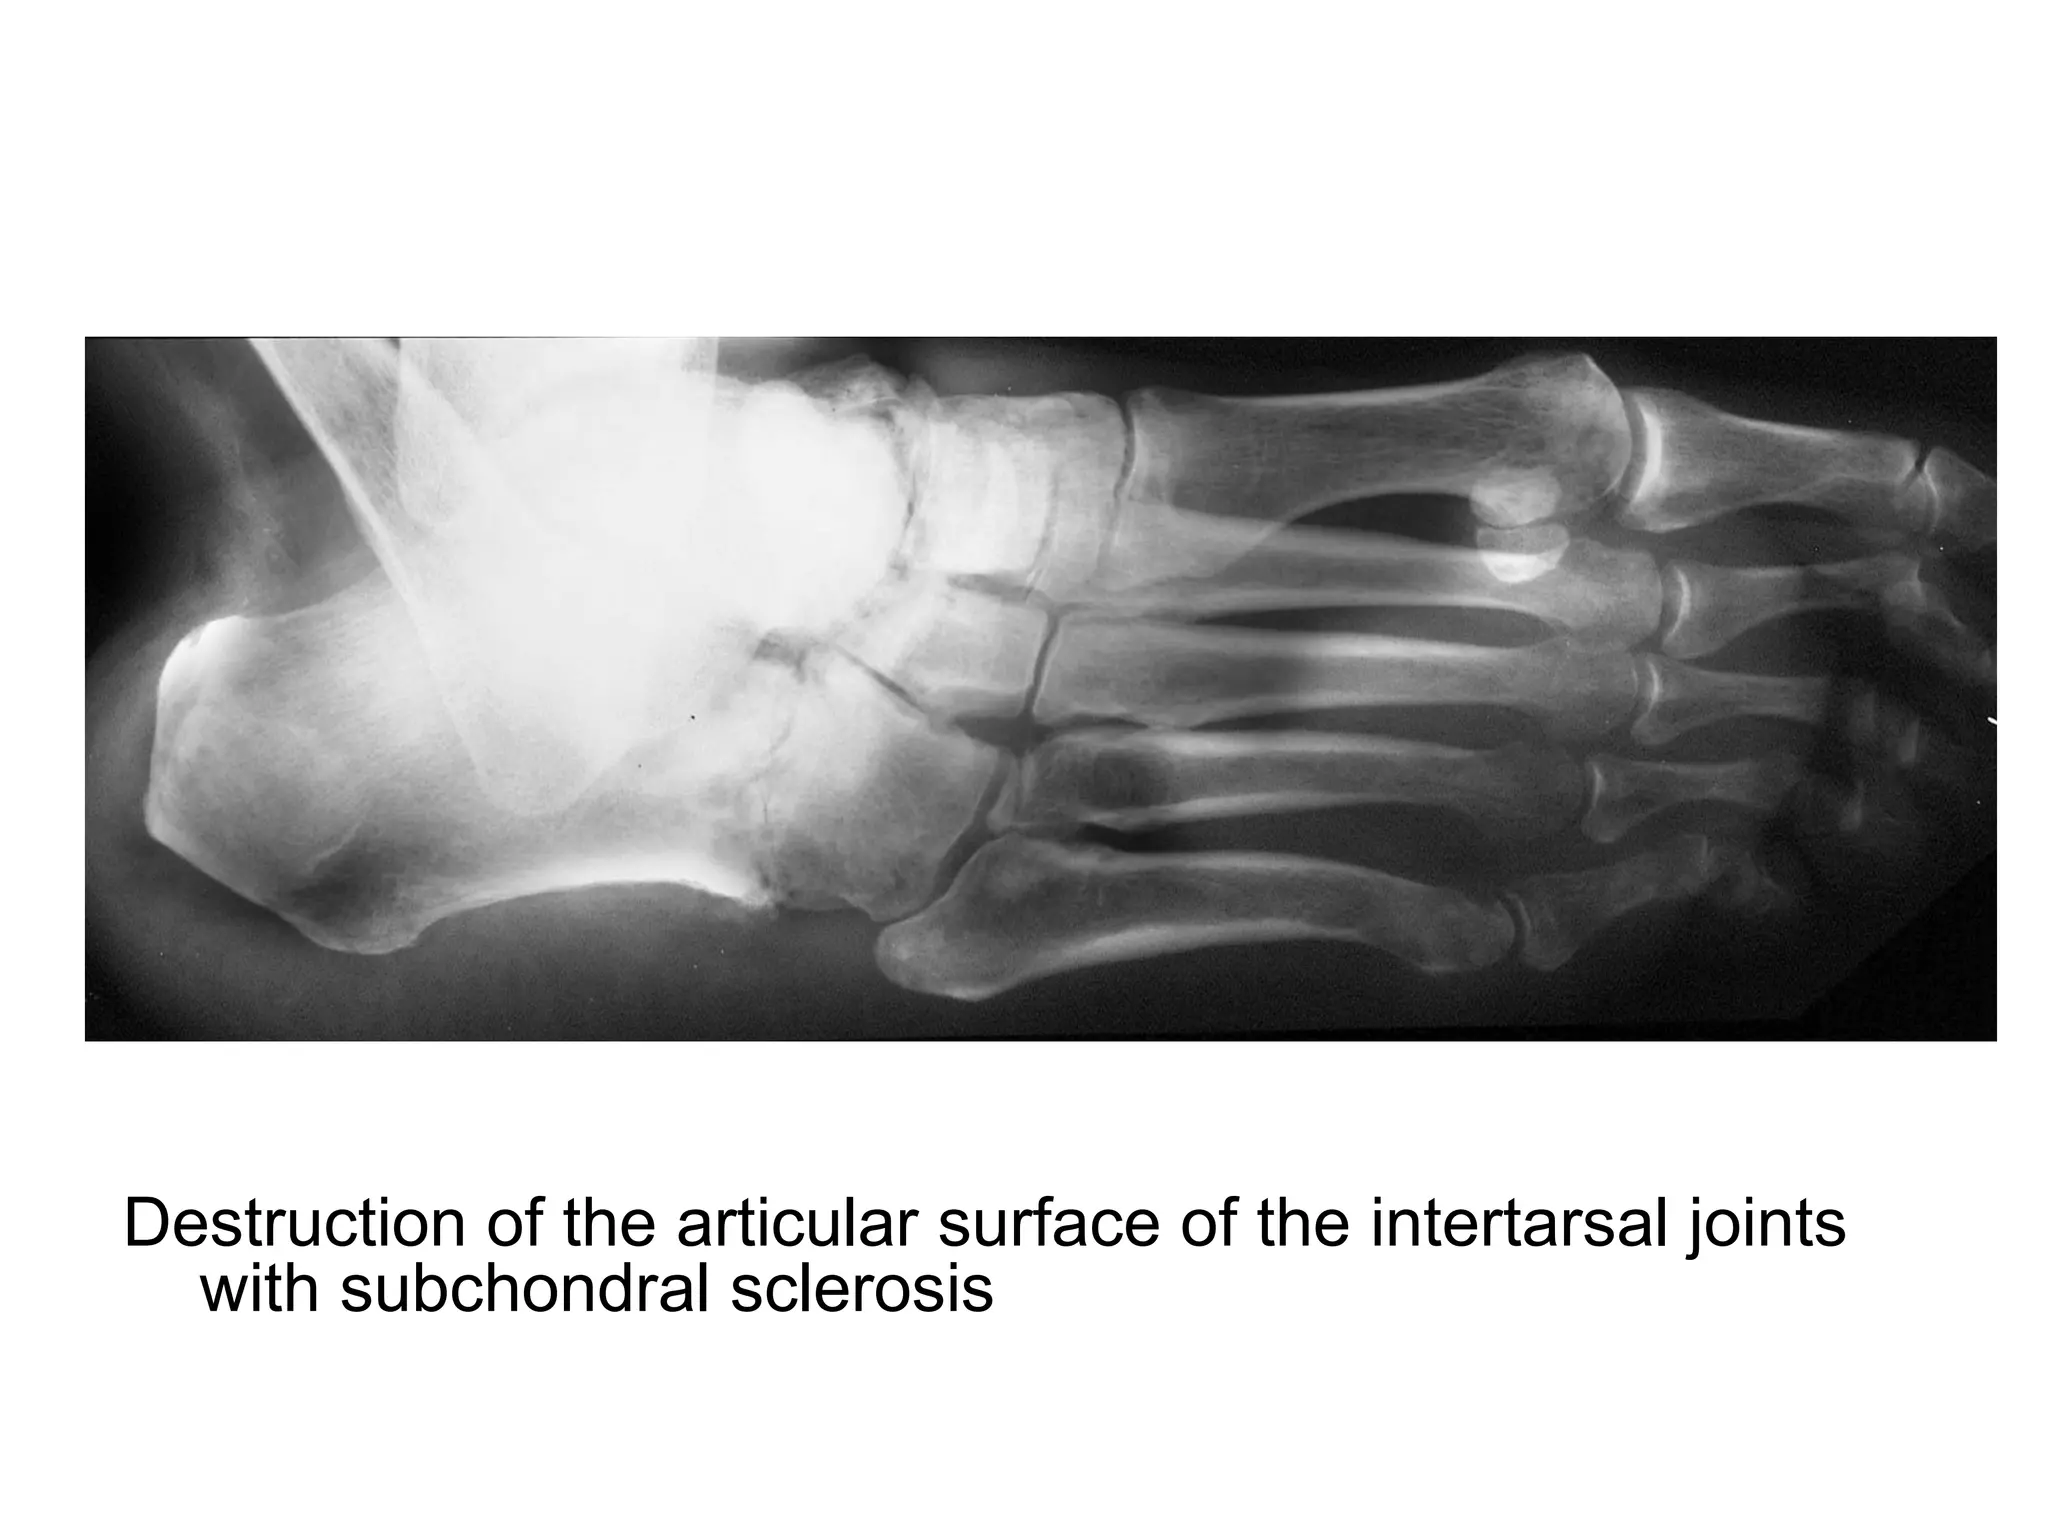

Destruction of the articular surface of the intertarsal joints

with subchondral sclerosis